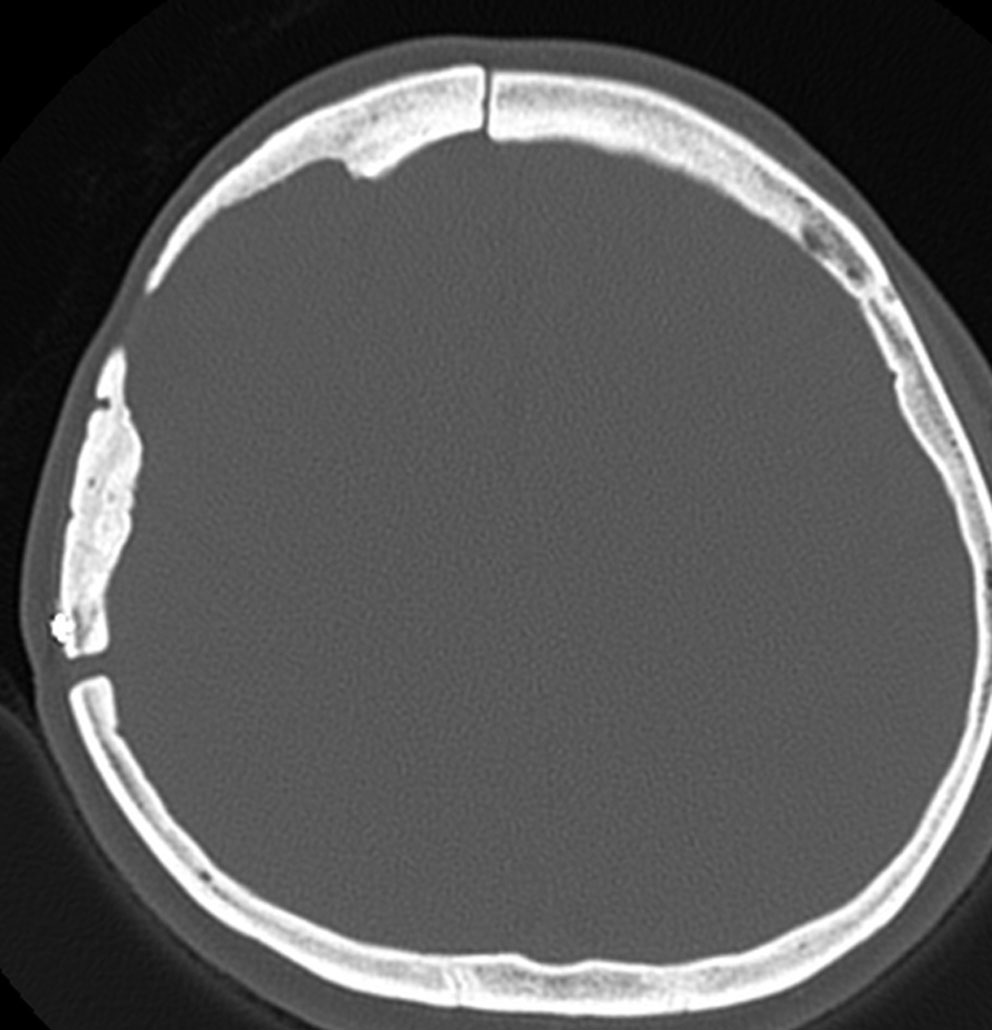

骨内髄膜腫 osseous meningioma

骨内増殖をする髄膜腫です。頭蓋骨腫瘍と間違えるようなものです。触った感じは骨腫ですが,CTでは,表面が毛羽立っていて,頭蓋冠に浸潤していることが特徴です。浅側頭動脈からの豊富な血流があります。

わずかですが頭蓋内にも腫瘍があり,硬膜が肥厚してガドリニウム増強されます。

頭蓋骨をかなり広範におかすので骨は捨てません。開頭して取り外した骨の厚くなっている部分と髄膜腫で軟らかくなっている部分を削除して,それから骨片をオートクレーブで短時間熱処理して,元あった所にもどします。下の画像は手術後1年半が経過したものですが,髄膜腫の再発はなく,熱処理骨弁は吸収されないで生着しています。